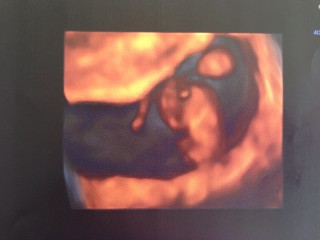

45歳の高齢初産になる私です。今日初めてエコー診断に行きました。小さな命が心臓を1分間に164回も打ちながら、頑張って生きているのを見て思わず涙が(^^) 心配はたくさんあるけど、ポジティブに赤ちゃんと一緒に頑張って行きます。

この日に胎児の心拍を目で確認する事ができました。

音は聞いていないものの赤ちゃんの真ん中辺りで

動く心臓を発見!

波形にした心拍を見る事も出来ました!